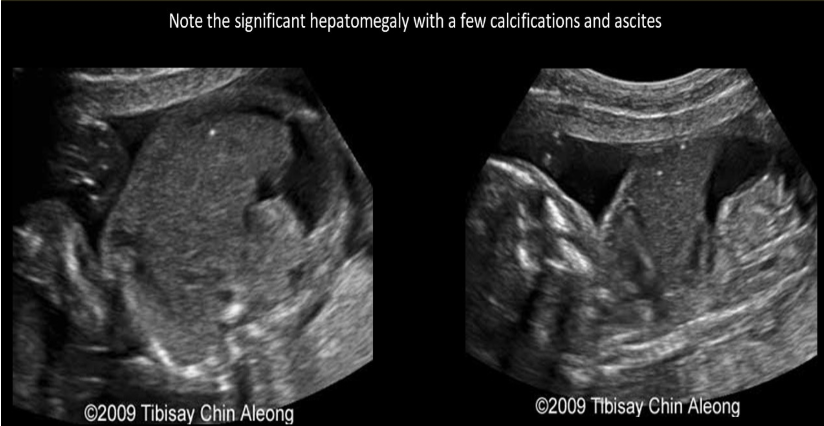

which is most likely to cause polyhydramnios, fetal ascites, and hepatomegaly

.

a) parvovirus infection

b) IUGR

c) potter syndrome

d) autosomal recessive PKD